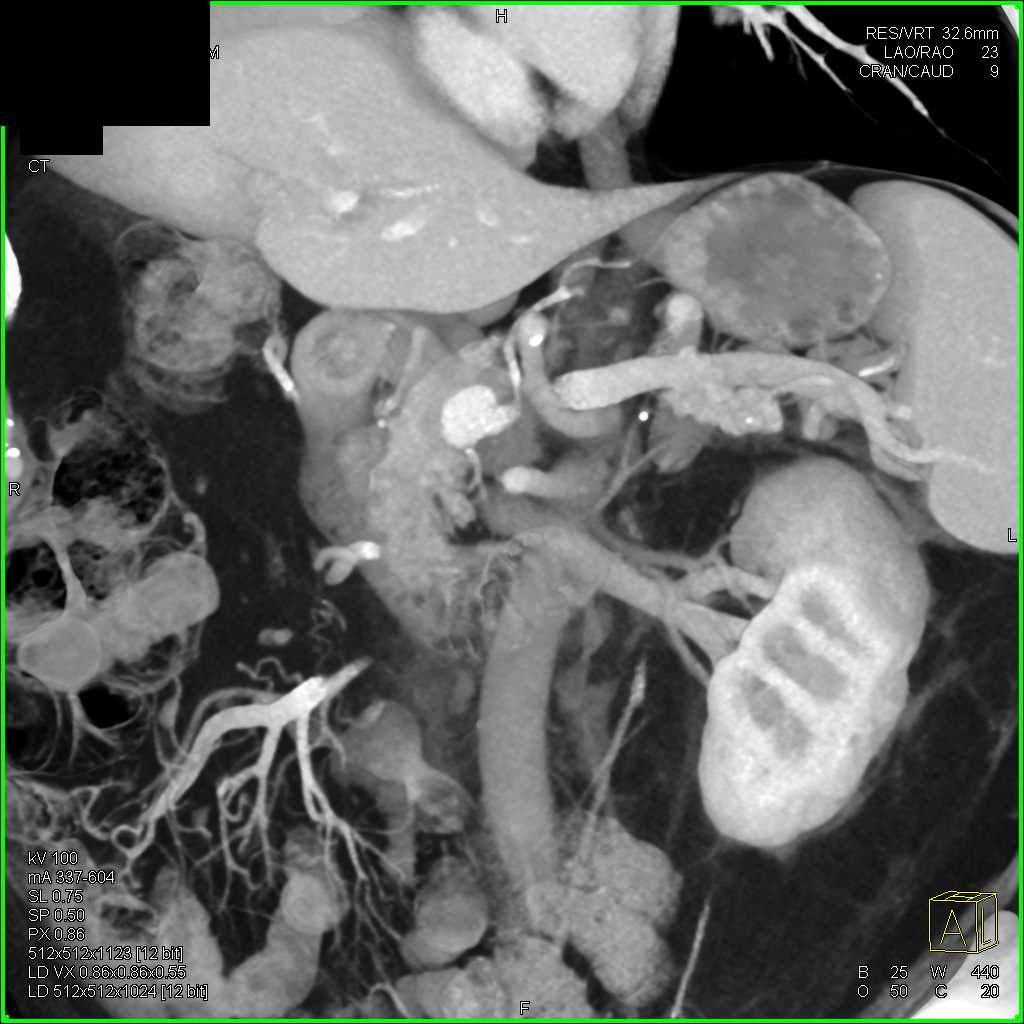

Carcinoma Head of the Pancreas